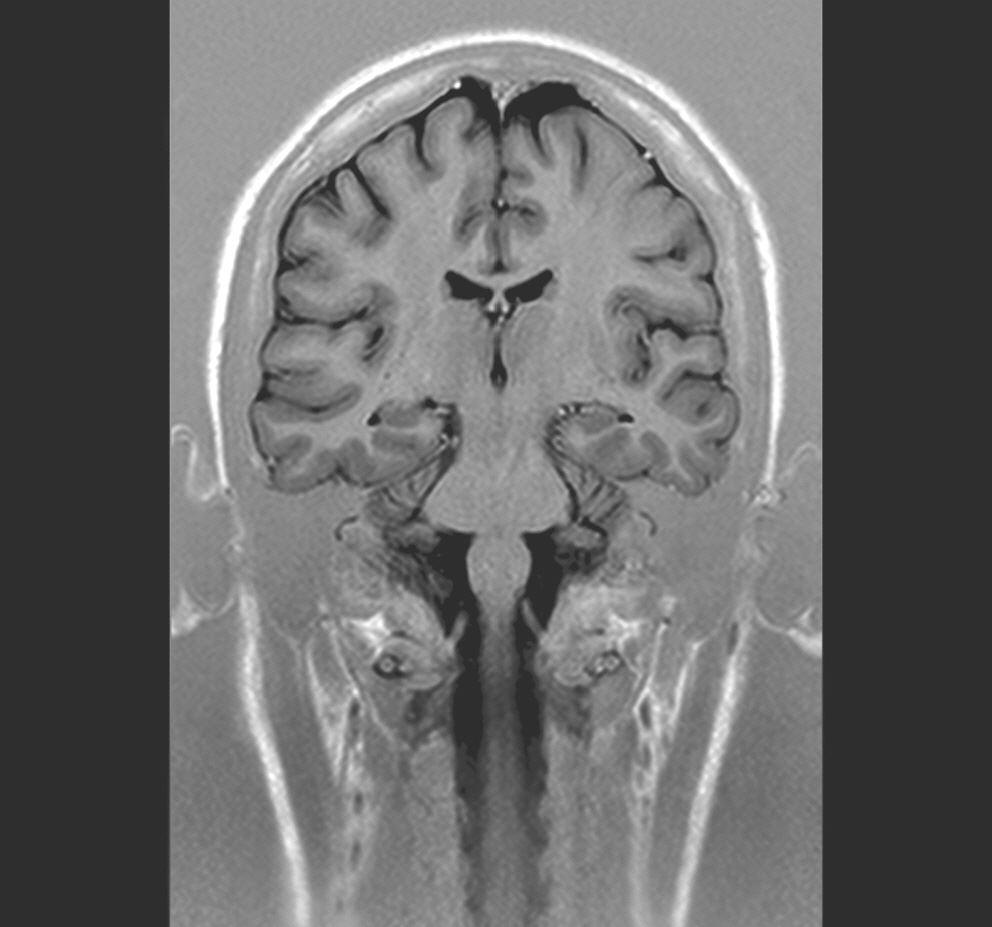

MRT Kopf coronar

Das gilt nicht nur für das Gehirn, sondern auch für den Rückenmarkskanal und das darin verlaufende Rückenmark sowie die Nervenwurzeln.

Besondere Untersuchungssequenzen existieren für die Darstellung von Entzündungen, Blutungen oder Tumoren, zur Epilepsiediagnostik oder zur Abklärung von Durchblutungsstörungen. Frühzeitig können Schlaganfälle beurteilt werden und ursächliche Verengungen der Blutgefäße gleich mit dargestellt werden (MR-Angiographie).